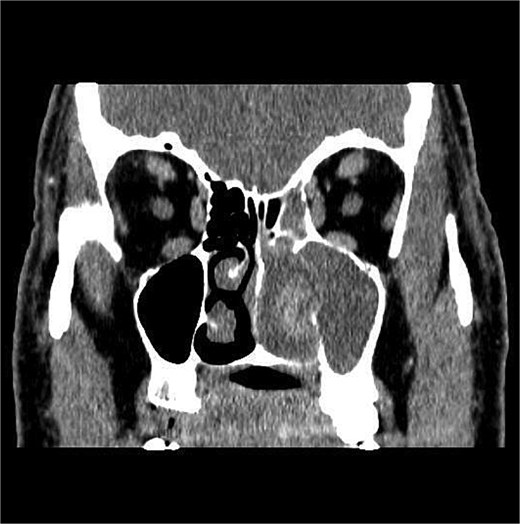

The patient underwent staging CT which was negative for distant metastasis. He then went underwent incomplete medial maxillectomy, ethmoidectomy, and sphenoidotomy followed by 10 sessions of immunotherapy abroad. He presented to our institution for follow up 6 months later with history of left nasal block and epistaxis. Nasal flexible scope showed a reddish nasal mass with greenish secretions (Fig. 3). Follow up CT revealed tumor recurrence (Figs 4 and 5). He was advised for multidisciplinary team evaluation to plan the treatment but he refused any intervention and lost follow up.

Coronal section of CT paranasal sinus soft tissue window showing the mass occupying the left nasal cavity and extending to maxillary and ethmoidal sinus, and reaching base of skull.